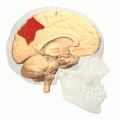

![]() Sagittal MRI slice with the precuneus shown in red. (Anterior to the left.) | |

Precuneus of left cerebral hemisphere (shown in red). -